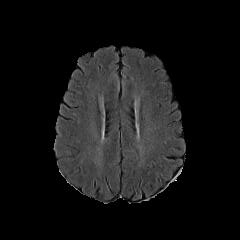

Refer to caption

(e) Normal Liver

(f) Normal Liver

(g) Liver Tumor

(h) Liver Tumor

Figure 4: We show some example brain MRI slices from BratS18 (first row) and Liver CT slices from LiTS (second row). Both normal- and abnormal-looking images are provided.

Aside from the difference in imaging tissue and modality of these two data sets, the tumor regions on the CT images are of different shape and size, as can be seen in Figure 4. Also, many CT scans are acquired in a way that introduces greater noise-like artifacts than MRI. For each dataset, 80%percent8080\% of randomly selected data are used for training and the resting 20%percent2020\% for testing.